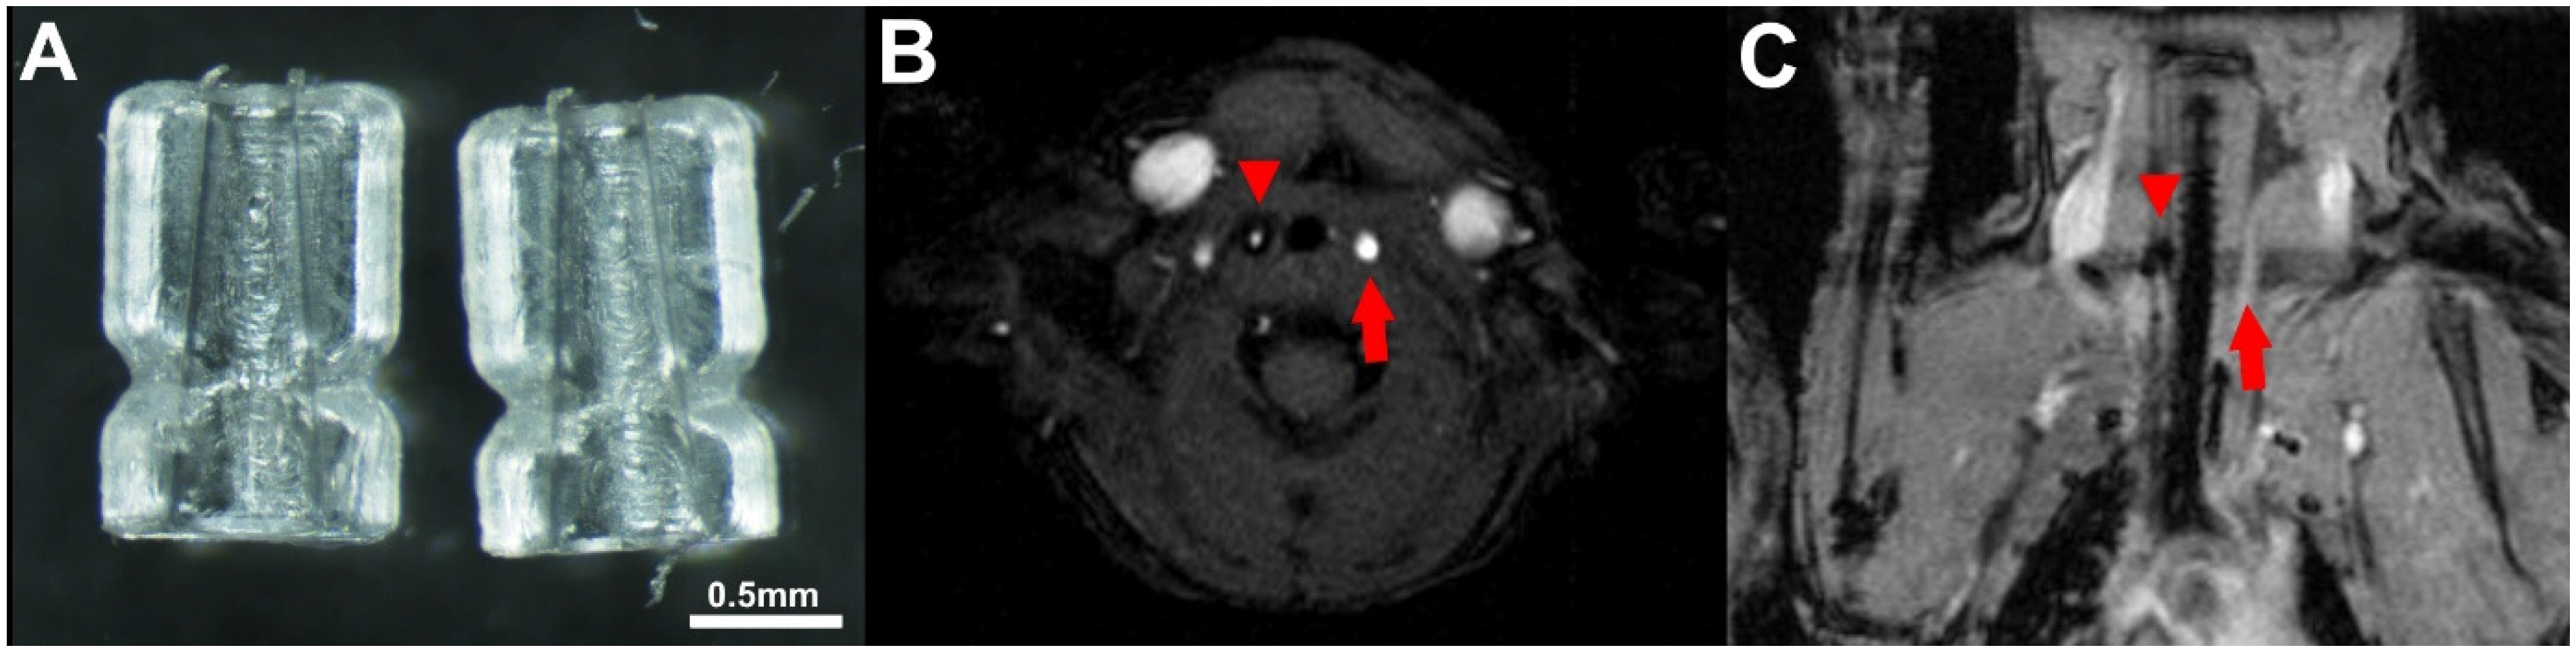

- Kuhlmann, M.T.; Cuhlmann, S.; Hoppe, I.; Krams, R.; Evans, P.C.; Strijkers, G.J.; Nicolay, K.; Hermann, S.; Schäfers, M. Implantation of a carotid cuff for triggering shear-stress induced atherosclerosis in mice. J. Vis. Exp. 2012, 59, e3308. [Google Scholar]